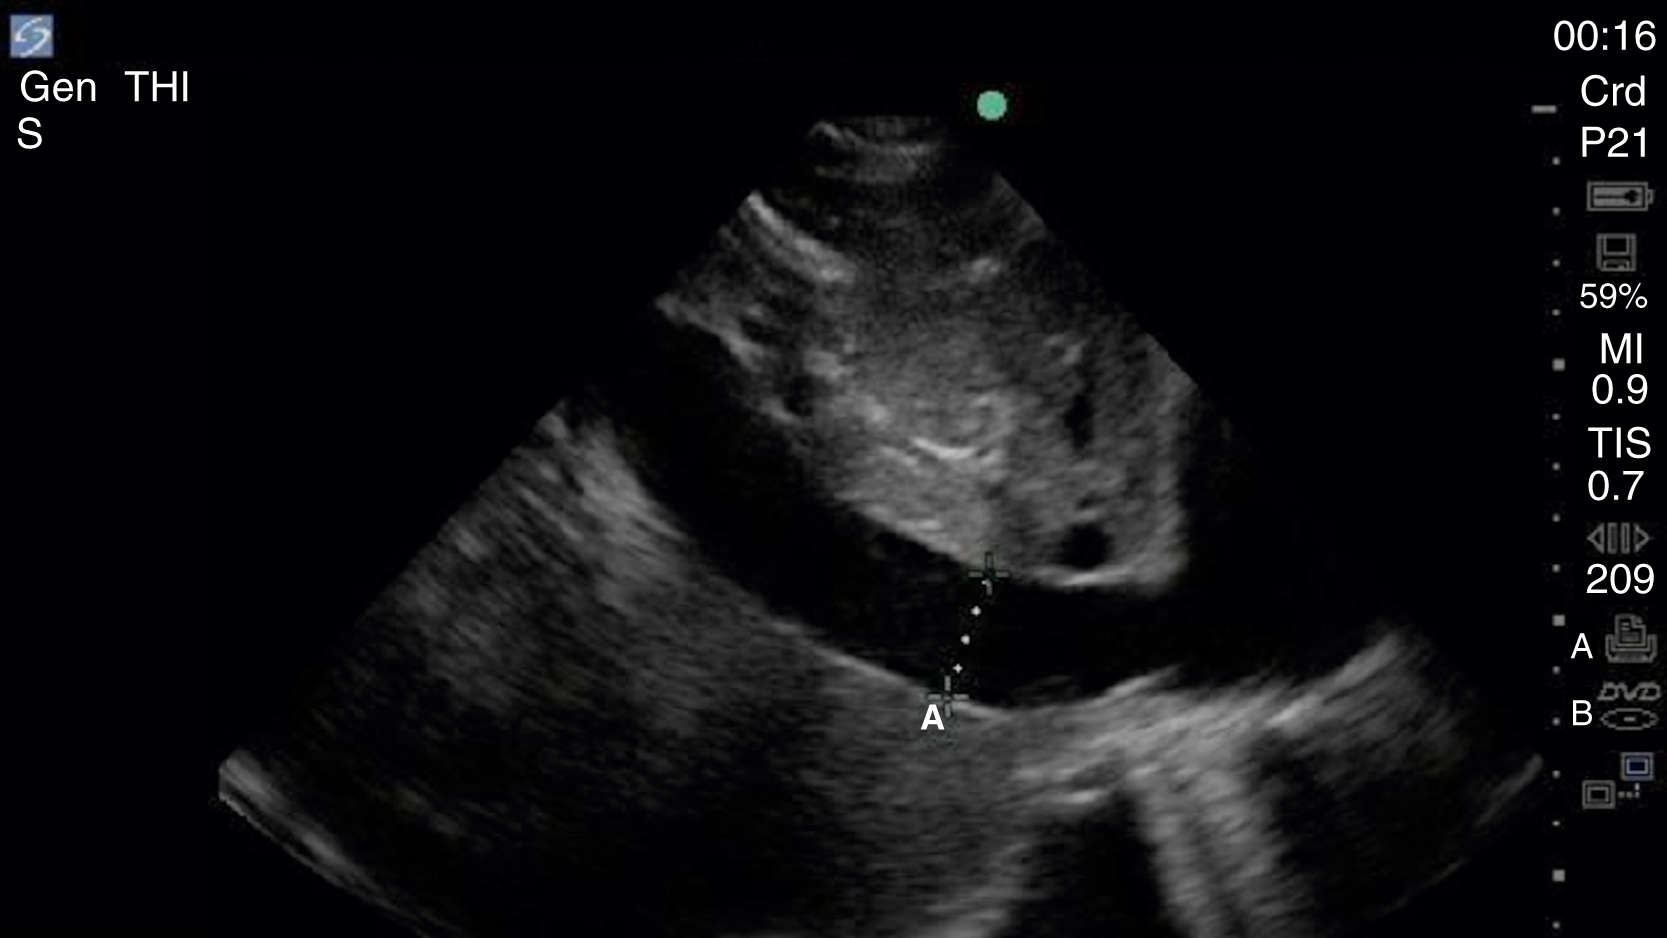

Image Acquisition

Cardiac US is performed through the transthoracic and transabdominal windows with the use of small curvilinear or phased array transducers. Typical views include the subcostal four-chamber view (subxiphoid), parasternal long-axis view ( Fig. e3.10 ; see Video e3.4 ), parasternal short-axis view, and apical four-chamber view. The subcostal four-chamber view, as in the FAST, is ideal for assessment of pericardial effusion and useful during cardiac arrest because it does not interfere with chest compressions. The long-axis subcostal view highlights the inferior vena cava (IVC) and can indicate volume status. The parasternal views are excellent windows for LV assessment. The apical four-chamber view is ideal for comparison of RV and LV sizes and function. Several US protocols have been developed to evaluate undifferentiated hypotension and can be used to narrow the differential diagnosis.

Normal parasternal long-axis view of the heart.

Pericardial fluid is typically anechoic, although it can contain internal echoes in cases of pericardial hemorrhage or infection. Large pericardial effusions are usually circumferential but can be loculated. As a result, assessment for pericardial effusion should include multiple views, when feasible, to confirm diagnosis and to avoid mistaking the epicardial fat pad for a pericardial effusion. Although cardiac tamponade is a clinical diagnosis, there are several suggestive echocardiographic features, including diastolic collapse of the RV ( Video e3.9 ), loss of respiratory variation of the IVC ( Fig. e3.11 ), and transvalvular flow velocity paradoxus.

Plethoric IVC showing where to take a measurement.

Assessment for global LV systolic function can be performed with visual estimation ( Video e3.10 ) and/or assessment of E-point septal separation (EPSS). EPSS is the distance between the anterior mitral valve leaflet and the ventricular septum measured using M-mode. A distance greater than 7 mm is abnormal, with larger measurements correlating to worsening systolic function. Emergency clinicians should recognize that accurate visual estimation of global LV systolic function requires experience and may prefer to categorize systolic function dichotomously as depressed or normal.